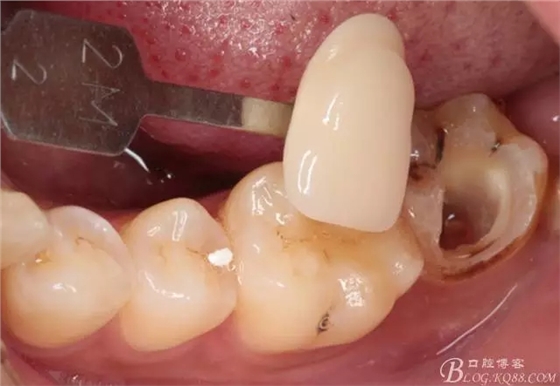

去除暫封物,拍照,比色。

流動(dòng)樹脂充填窩洞,金霸王車針和鎢鋼車針常規(guī)備牙,配合硅膠尖拋光,頰側(cè)排00排齦線。硅橡膠二次法取模,記錄咬頜關(guān)系,臨時(shí)樹脂充填窩洞。